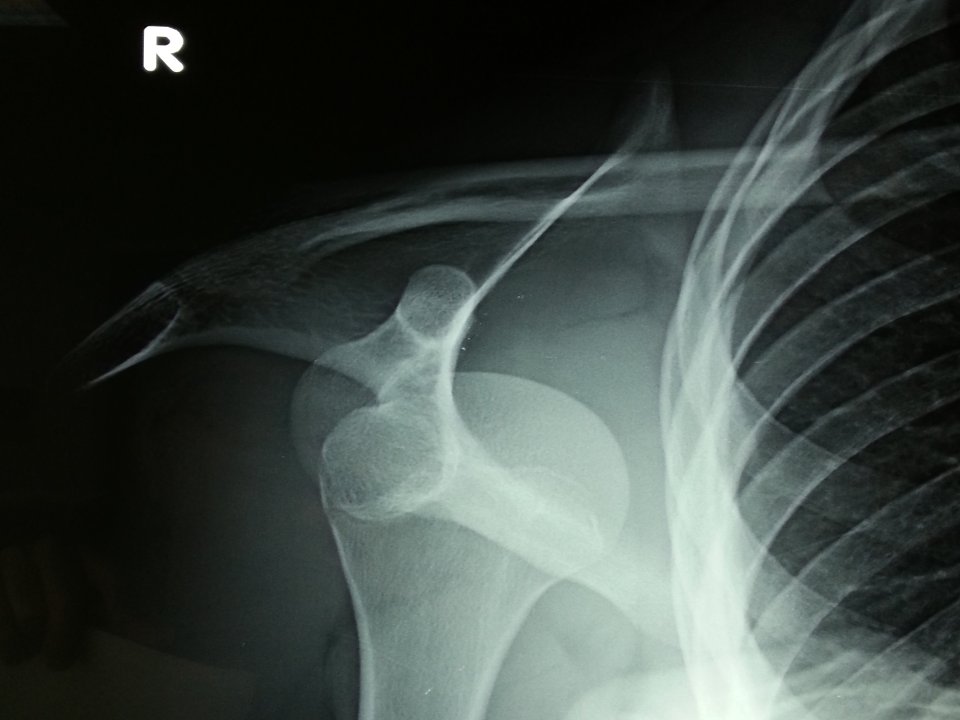

Εξάρθρημα ώμου – αστάθεια

Η άρθρωση του ώμου είναι η πιο ευκίνητη άρθρωση στο ανθρώπινο σώμα. Δυστυχώς όμως η περισσότερη ευκινησία συνεπάγεται και λιγότερη σταθερότητα. Έτσι, διάφορα αθλήματα αλλά και δραστηριότητες της καθημερινής ζωής θέτουν υψηλές απαιτήσεις από την άρθρωση του ώμου εξωθώντας την πολλές φορές πέρα από τα όρια της σταθερότητάς της.